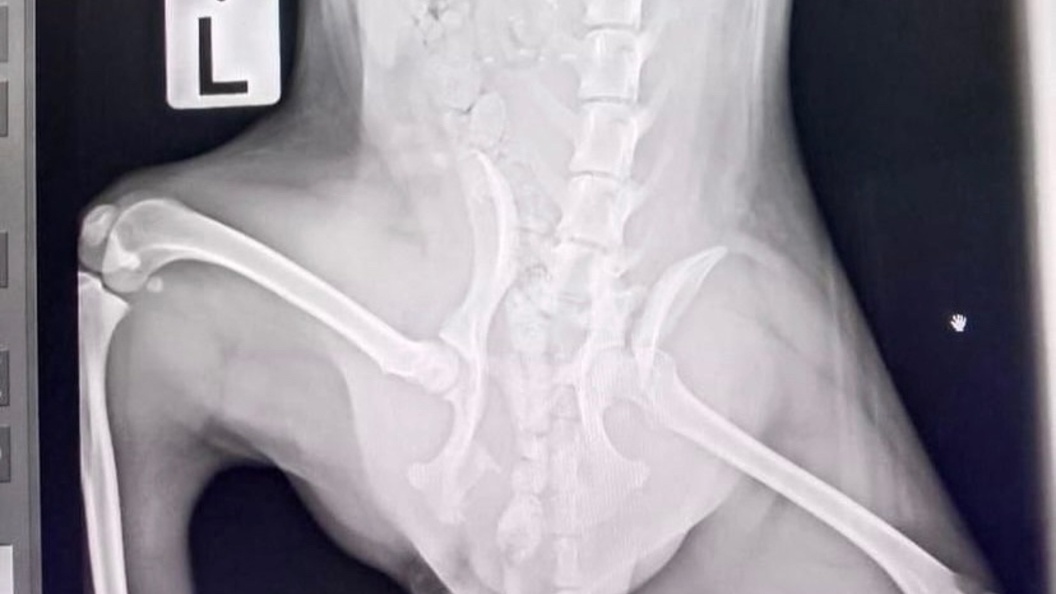

Фото: "Потеряшки Краснодара"/vk.com/public65863089

Спустя четыре дня избитое животное приползло на соседский участок за помощью. 15 сентября его доставили в ветеринарную клинику. У пса диагностировали множественные переломы, ушибы и раны. Правоохранители разбираются в обстоятельствах произошедшего.